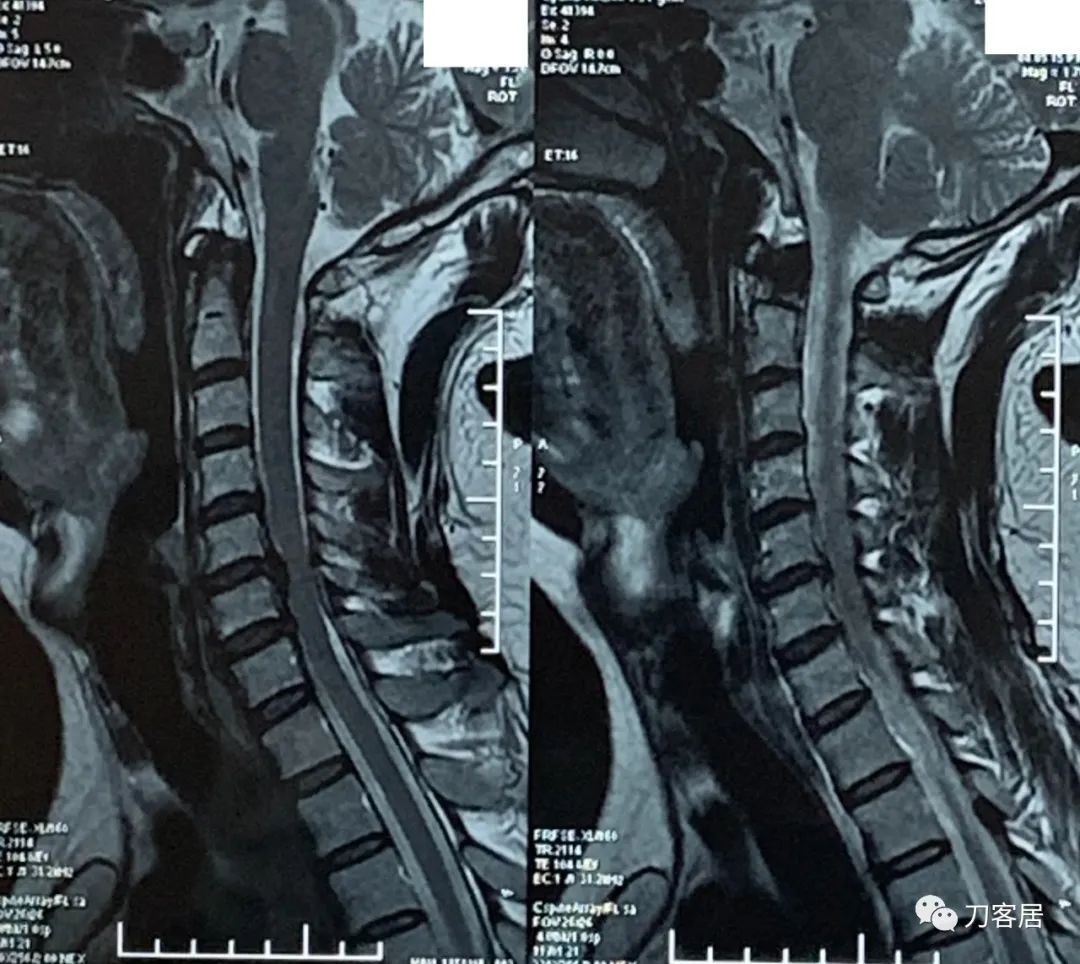

图1. 20220305颈椎MRI提示颈5-6椎间盘突出,椎管狭窄,脊髓受压。

图2. 20220305颈椎MRI提示颈5-6椎间盘突出,椎管狭窄,脊髓受压。

自带颈椎MRI提示颈5-6椎间盘突出,不严重。